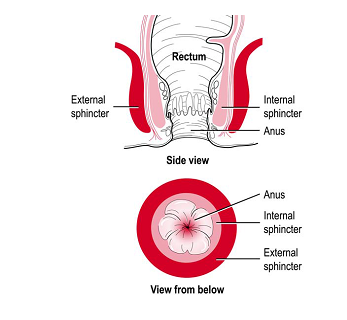

Sphincter

Decreases size of opening.